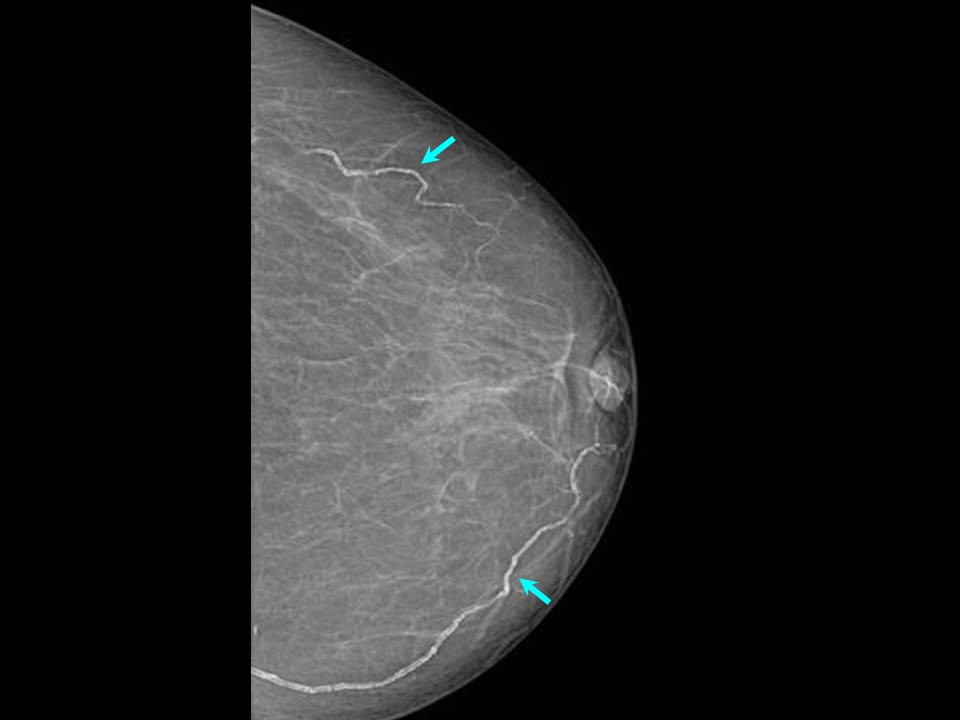

CALCIUM ON BREAST Vascular Breast Calcifications Are Benign, Breast

Calcifications Milk of Calcium Radiology Key What Do Calcium Deposits In The Breast Mean As breast cells grow and divide, calcium deposits can build up in breast tissue. They’re common and often show up on a routine. Called calcifications, these deposits can appear as bright white specks in mammograms. Breast calcifications are calcium deposits that develop in breast tissue. They appear as white spots or flecks on a mammogram. They are usually harmless, but. What Do Calcium Deposits In The Breast Mean.

CALCIUM ON BREAST Vascular Breast Calcifications Are Benign, Breast What Do Calcium Deposits In The Breast Mean Calcifications have different characteristics that indicate. In some instances, certain types of. Breast calcifications are calcium deposits within breast tissue. Breast calcifications are calcium deposits that are found in breast tissue and are fairly common, especially in women older than 50. Called calcifications, these deposits can appear as bright white specks in mammograms. They are very common and are usually. What Do Calcium Deposits In The Breast Mean.